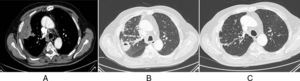

A) Masa pulmonar en la periferia del LSD con centro hipodenso, de aspecto necrótico-abcesificado, con una pequeña burbuja aérea en su interior (imagen TC en ventana mediastino). B) Desaparición de la imagen previamente descrita, con aparición de un nuevo nódulo pulmonar cavitado en la proximidad. Se observan también la presencia de engrosamientos de paredes bronquiales e impactaciones bronquiolares en LSD (imagen TC en ventana pulmón). C) Desaparición de los hallazgos previos (imagen TC de control en ventana pulmón).

Varón de 70 años con antecedentes de CU estable los últimos 5 años bajo tratamiento con azatioprina. Consultó por cuadro de hemoptisis. Se realizó tomografía computarizada (TC) torácica que detectó nódulo cavitado de 18mm en lóbulo inferior derecho. Al mes, se realizó PET-TC que objetivó crecimiento (19,5mm) e hipermetabolismo (SUV 5,77) del nódulo. Broncoscopia sin alteraciones y estudio funcional respiratorio con leve alteración no obstructiva (FEV1/FVC 77, FEV1 [L] 2,22 [68%], FVC [l] 2,89 [65%]). Estudio microbiológico de las muestras endoscópicas, con auramina y detección de ácidos nucleicos para M. tuberculosis complex, negativos. Cuatro semanas después, el paciente presenta nuevo episodio de hemoptisis e insuficiencia respiratoria (pO2 de 52mmHg). Una nueva TC torácica objetiva masa de 7cm en lóbulo superior derecho (LSD) (fig. 1A). El estudio con contraste descartó tromboembolismo pulmonar. Se repitió la broncoscopia, de nuevo normal, con resultados negativos para citología y microbiología (detección directa y cultivos para bacterias, hongos y micobacterias). Ante la sospecha de absceso pulmonar, se inició tratamiento con clindamicina con una correcta evolución clínica. Sin embargo, la TC torácica de control a los tres meses objetivó resolución de dicha lesión con aparición de nueva imagen cavitada en el LSD (fig. 1B). Para descartar relación con la enfermedad intestinal, se realizó una colonoscopia que evidenció CU leve. Además, el estudio inmunológico (incluyendo anticuerpos anti-nucleares y anti-citoplasma) fue negativo.

Dada la ausencia de diagnóstico se decidió la realización de biopsias pulmonares mediante toracotomía. La anatomía patológica evidenció acúmulos estériles de neutrófilos con áreas de necrosis y focos de neumonía organizada, sin evidencia de infiltración vascular. Estos hallazgos se interpretaron como compatibles con afectación pulmonar por su CU. Se inició tratamiento con prednisona 30mg cada 12h durante 2 semanas con resolución completa de las imágenes radiológicas (fig. 1C).